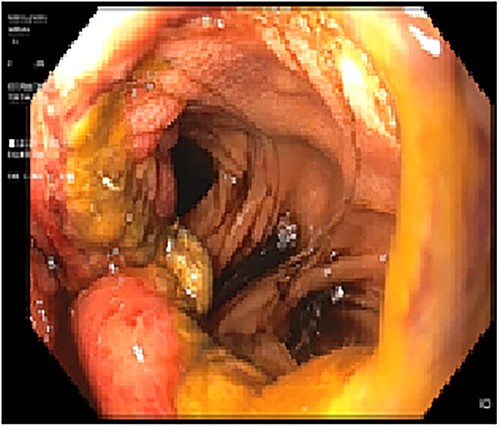

A 29-year-old woman originally from Ecuador’s Amazon region who presented with a history of grade II obesity (body mass index of 37) had undergone bariatric surgery (OAGB) 30 days before admission to our hospital. The patient showed intolerance to a liquid diet and symptoms of reflux starting at the immediate postoperative period, in addition to repeated bilious vomiting after progression to a semisolid diet. Physical examination showed normal vital signs, the abdomen was tender without signs of peritoneal irritation. The protein profile showed alterations with evidence of malnutrition. Abdominal Computed Tomography showed evidence of efferent intestinal loop bending with decreased passage of enteric contrast (Fig. 1A and B). An endoscopy showed stenosis of the gastroenteric anastomosis and obstruction of the efferent loop (Fig. 2).

(A) Computed Tomography: Afferent loop bending and gastroenteric anastomotic stenosis. (B) Radiograph showing distal efferent obstruction.

Upper gastrointestinal endoscopy showing gastroenteric anastomotic stenosis.